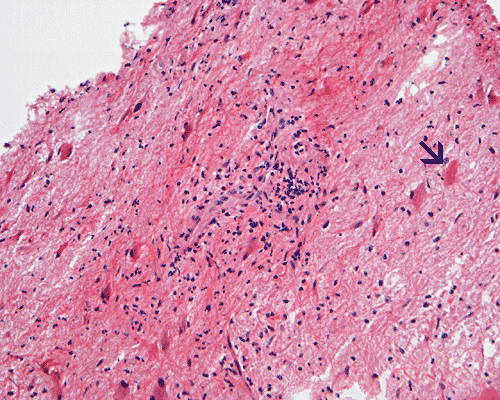

Panel A to E are MR images. Panel F and G are taken from intraoperative cytologic preparation. Panel H to M are taken from frozen section. Panel N and O are from paraffin section. These sections are stained by hematoxylin-eosin stain. Panel P is immunohistochemistry for neurofilament proteins. Panel Q is stained by Luxol fast blue-Periodic acid Schiff (LFB-PAS) stain.

The segment of spinal cord at T3-T4 level is expanded and is accompanied by edema that runs from T2-T6. The expansion and edema is roughly symmetrical along the long axis of the cord. The expanded levels are isointense to the white matter of the spinal cord on T1-weighed images (Panel A). The edema is best demonstrated on T-weighed images (Panel B, C, and E). Patchy and poorly defined enhancement is demonstrated in the expanded areas (Panel D). The remaining levels of the spinal cord and the brain are free of abnormal changes.